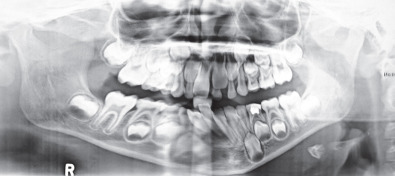

Plain films of the craniofacial skeleton, especially the midface, are of no use in the assessment of facial trauma in the pediatric population. Developing sinuses and tooth buds may obscure already overlapping planes. Computed tomography (CT) scans are necessary in order to accurately diagnose pediatric facial trauma. Fine facial cuts are necessary to adequately define facial fractures, and 3D reconstructions can be extremely useful in planning surgical intervention and teaching trainees. Cone beam CT scans and orthopantomograms (panoramic radiographs or panorex) are also useful to assess for dental injuries.

Physical examination is focused on the zone of trauma. Overlying lacerations, ecchymosis and soft tissue disruption may give clues as to directed injuries. Due to the lack of pneumatization of the sinuses and strength from unerupted tooth buds, forces applied to the midface are transferred to the dentoalveolar complex resulting in tooth avulsion and fractures. Dentoalveolar fractures are the commonest form of pediatric midface fractures and occasionally may be associated with midface gingival degloving ( Fig. 2.4.5 ). An understanding of the patterns of tooth eruption will be useful in assessing children between ages 6 to 12 in mixed dentition ( Fig. 2.4.6 ).

Maxillomandibular fixation (MMF) in children with deciduous or mixed dentition can prove challenging ( Fig. 2.4.7 ). The conical shape of the primary teeth and partially erupted permanent teeth may be difficult to adequately fixate with interdental wires and arch bars. Likewise, use of MMF screw fixation may be limited given the various permanent tooth buds present in both the maxilla and mandible. In very young children, temporary suspension wiring around the zygomatic arch or piriform aperture to the arch bar may be necessary for fixation. Fortunately, major midface fractures affecting occlusion and mandibular fractures are more common in patients with more mature dentition, such as adolescents and teenagers.